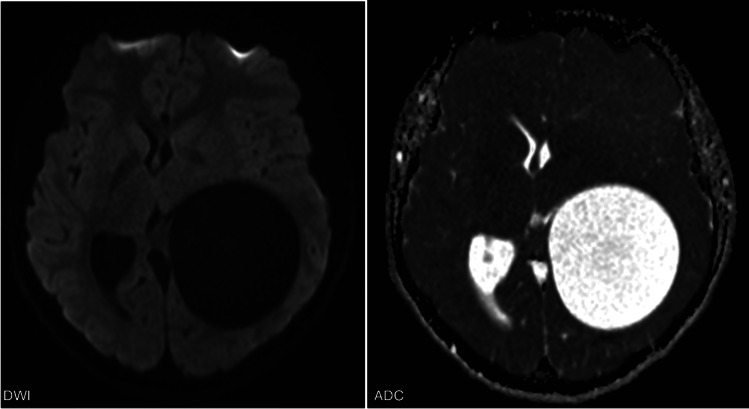

教学要点:当怀疑有脑包虫病时,需要胸腹影像学检查颅内外病变。当发现无并发症的轴内囊肿时,应鉴别诊断包虫病,特别是来自或有流行地区旅行史的患者,或已知接触过狗、羊或牛的患者。胸腹影像可能有助于诊断,因为包虫病更常累及肝脏和肺部,很少累及大脑。

Teaching point: When hydatid disease in the brain is suspected, thoraco-abdominal imaging is warranted to detect extracranial lesions. When an uncomplicated intra-axial cyst is encountered, hydatid disease should be in differential diagnosis, especially in patients from or with travel history to endemic areas, or with known exposure to dogs, sheep or cattle. Thoraco-abdominal imaging may aid diagnosis as hydatid disease more commonly affects the liver and lungs and only rarely the brain.